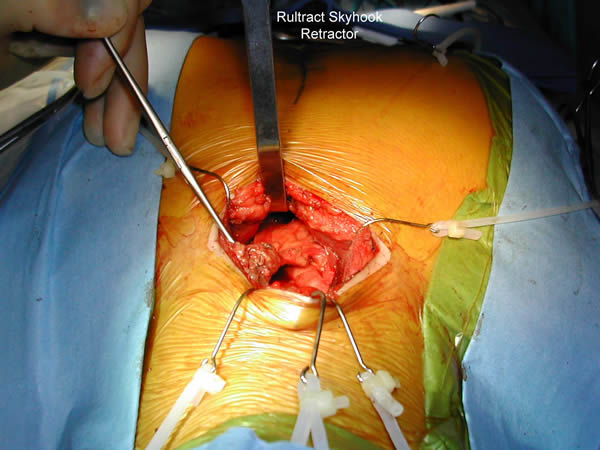

The plane just posterior to the sternum is developed bluntly with a finger and the Rultract retractor is placed and the skyhook used to elevate the sternum (Figure 5A & B, Video 3) [1]. The inflatable pressure bag posterior to the patient is now deflated, allowing the anterior mediastinum to further expand as the middle mediastinum falls away.

| Figure 5a & 5b: Rultract retractor in place. |